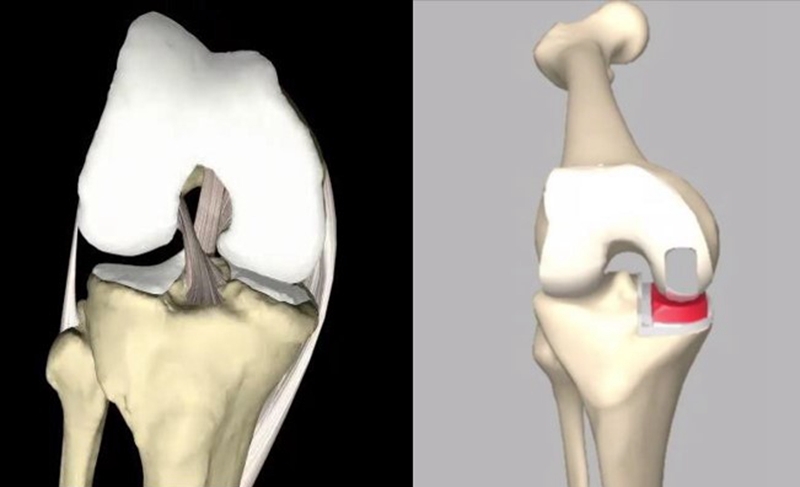

OUKA垫片的设计和稳定:

①半月板-股骨(球-臼):屈伸运动;

②半月板-胫骨(平-平):水平+旋转运动;

③活动型垫片随股骨假体而运动。

锁扣机制:当股骨假体位置安放准确,衬垫对线良好,这种机制才有效

①在膝关节最后伸直的15~20°;

②垫片随股骨假体存在内旋;

③垫片前内侧可超出胫骨平台前缘甚至悬空。